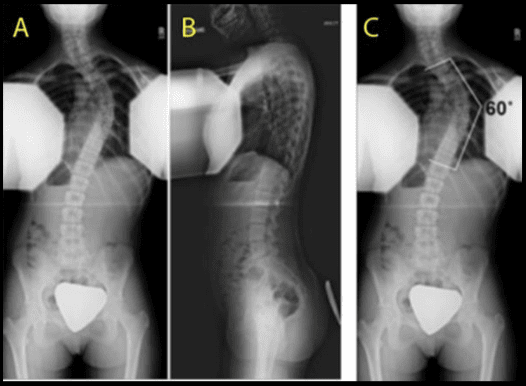

Studji dwar l-Immaġini

L-immaġini f'mard deġenerattiv tad-diska tintuża prinċipalment biex tiddeskrivi relazzjonijiet anatomiċi u karatteristiċi morfoloġiċi tad-diski affettwati, li għandha valur terapewtiku kbir fit-teħid ta 'deċiżjonijiet futuri għal għażliet ta' trattament. Kwalunkwe metodu ta 'immaġini, bħal radjografija sempliċi, CT, jew MRI, jista' jipprovdi informazzjoni utli. Madankollu, kawża sottostanti tista 'tinstab biss fi 15% tal-pazjenti billi l-ebda bidliet radjoloġiċi ċari ma huma viżibbli f'mard deġenerattiv tad-diska fin-nuqqas ta' ħernja tad-diska u defiċit newroloġiku. Barra minn hekk, m'hemm l-ebda korrelazzjoni bejn il-bidliet anatomiċi li dehru fuq l-immaġini u s-severità tas-sintomi, għalkemm hemm korrelazzjonijiet bejn in-numru ta 'osteofiti u s-severità ta' uġigħ fid-dahar. Bidliet deġenerattivi fir-radjografija jistgħu jidhru wkoll f'nies bla sintomi li jwasslu għal diffikultà biex jikkonformaw ir-rilevanza klinika u meta tibda l-kura. ("Marda tad-Diska Deġenerattiva" Fiżjopedja)

Ir-Radjografija

Din ir-radjografija ċervikali sempliċi rħisa u disponibbli b'mod wiesa 'tista' tagħti informazzjoni importanti dwar id-deformitajiet, l-allinjament, u bidliet deġenerattivi taż-żaqq. Sabiex tiġi ddeterminata l-preżenza ta 'instabilità ta' l-ispina u bilanċ sagittali, għandhom isiru studji ta 'flessjoni dinamika jew estensjoni.

Immaġini b'Reżonanza Manjetika (MRI)

L-MRI huwa l-iktar metodu użat komunement għad-dijanjosi ta 'bidliet deġenerattivi fid-diska intervertebrali b'mod preċiż, affidabbli, u l-iktar komprensiv. Jintuża fl-evalwazzjoni inizjali ta 'pazjenti b'uġigħ fl-għonq wara radjografija sempliċi. Jista 'jipprovdi immaġini mhux invażivi f'diversi pjanuri u jagħti immaġini ta' kwalità eċċellenti tad-diska. L-MRI tista 'turi l-idratazzjoni tad-diska u l-morfoloġija bbażata fuq id-densità tal-proton, l-ambjent kimiku, u l-kontenut ta' ilma. L-istampa klinika u l-istorja tal-pazjent għandhom jiġu kkunsidrati meta jiġu interpretati r-rapporti tal-MRI peress li ntwera li sa 25% tar-radjoloġisti jibdlu r-rapport tagħhom meta d-dejta klinika tkun disponibbli. Fonar ipproduċa l-ewwel skaner MRI miftuħ bil-kapaċità tal-pazjent li jiġi skannjat f'pożizzjonijiet differenti bħal wieqaf, bilqiegħda u liwi. Minħabba dawn il-karatteristiċi uniċi, dan l-iskaner MRI miftuħ jista 'jintuża għall-iskannjar ta' pazjenti f'qagħdiet li jġorru l-piż u qagħdiet bil-wieqfa biex jindividwaw bidliet patoloġiċi sottostanti li ġeneralment jiġu injorati fl-iskan MRI konvenzjonali bħal mard deġenerattiv tal-ġenbejn bil-ħernja. Din il-magna hija tajba wkoll għal pazjenti klawstrofobiċi, peress li huma jaraw skrin kbir tat-televiżjoni waqt il-proċess tal-iskannjar. ("Marda tad-Diska Deġenerattiva: Sfond, Anatomija, Patofiżjoloġija.")

Nucleus pulposus u annulus fibrosus tad-diska jistgħu ġeneralment jiġu identifikati fuq l-MRI, u dan iwassal għall-iskoperta ta 'herniation tad-diska bħala kontenuta u mhux kontenuta. Peress li l-MRI tista 'turi wkoll tiċrit annulari u l-ligament lonġitudinali posterjuri, tista' tintuża biex tikklassifika l-herniation. Dan jista 'jkun minfuq annulari sempliċi biex tittrasferixxi l-hernjazzjonijiet tad-diska tal-frammenti. Din l-informazzjoni tista 'tiddeskrivi diski patoloġiċi bħal diski estrużi, diski maħruġa u diski migrati.

Hemm diversi sistemi ta 'klassifikazzjoni bbażati fuq l-intensità tas-sinjal MRI, l-għoli tad-diska, id-distinzjoni bejn in-nukleu u l-annulus, u l-istruttura tad-diska. Il-metodu, minn Pfirrmann et al, ġie applikat b'mod wiesa 'u aċċettat klinikament. Skont is-sistema modifikata, hemm 8 gradi għall-mard deġenerattiv tad-diska lumbari. Il-Grad 1 jirrappreżenta diska intervertebrali normali u l-grad 8 jikkorrispondi mal-istadju tat-tmiem tad-deġenerazzjoni, li juri l-progressjoni tal-marda tad-diska. Hemm immaġini korrispondenti biex jgħinu d-dijanjosi. Peress li jipprovdu differenzjazzjoni tajba tat-tessut u deskrizzjoni dettaljata ta 'l-istruttura tad-diska, l-immaġini mgħobbija T2 sagittali jintużaw għall-iskop tal-klassifikazzjoni. (Pfirrmann, Christian WA, et al.)